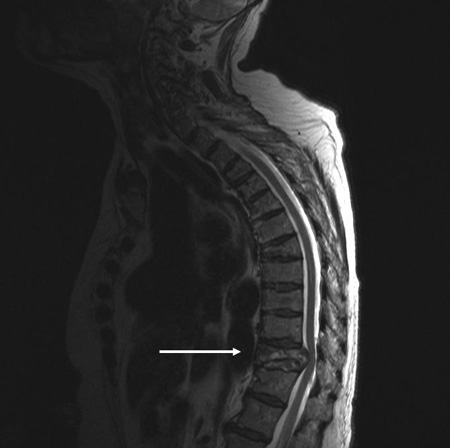

IRM de la columna torácica: vista sagital (secuencia ponderada en T2) con fractura patológica del cuerpo vertebral T10 causada por mieloma múltiple

De la colección personal del Dr. B. Nurboja y D. Choi